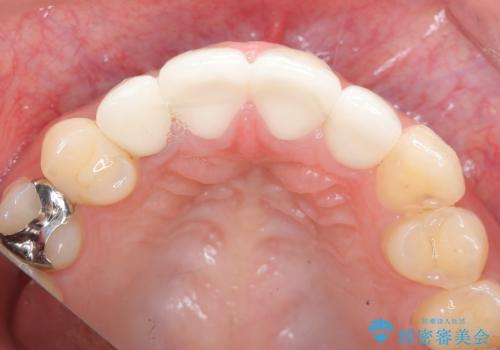

充填物や充填物下に再発した虫歯を丁寧に除去し、セラミッククラウンによる審美性の改善、虫歯治療を計画します。

- 52.8万円(ジルコニアクラウン×4・仮歯×4)費用は治療当時の料金となります

レジン修復による充填は、劣化し、色調の変化による審美障害が生じることが多々あります。

ある程度の大きさになった充填物は、劣化の少ないセラミッククラウンにすることで色調の劣化を抑え、審美性を保つことができます。